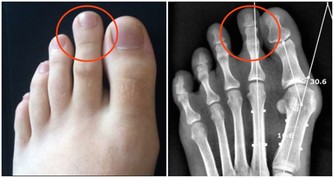

4、持續的腳痛或小腿疼痛

持續的腳痛或小腿疼痛,休息、服用布洛芬和撲熱息痛等均無效。

可能疾病:

應力性骨折(骨裂)。如果平時運動過多強度過大,骨骼沒有機會癒合,久而久之就會出現。

如何解決:

在骨裂癒合前要停止所有運動。及時就醫,情況嚴重的需要打幾周石膏。